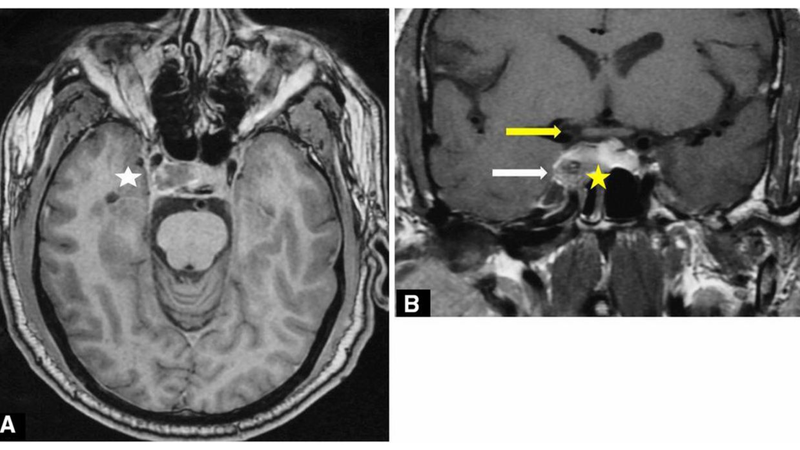

Liệt dây thần kinh số III có thể do bẩm sinh hoặc mắc phải. Nguyên nhân của liệt dây thần kinh số III do bẩm sinh cho đến nay vẫn chưa xác định được. Tuy nhiên, các nguyên nhân mắc phải dẫn đến liệt dây thần kinh số III đã được biết đến bao gồm:

Dây thần kinh số III bị liệt có thể do đột quỵ não, viêm não, viêm dây thần kinh, thiếu máu cục bộ vi mạch, u não, u màng não chèn ép,...